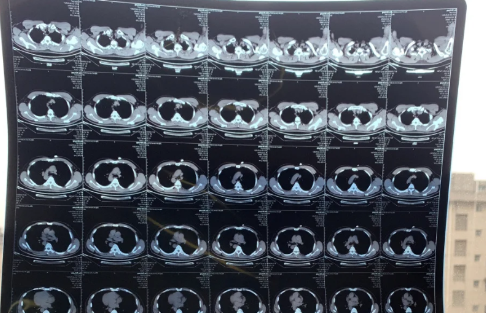

新冠白肺是比价常见的一个症状,现在无论老人还是年轻人如果新冠感染一直咳又不康复的话,可能会出现白肺或者肺炎的情况。那么,新冠白肺可逆吗?84岁老人肺全白有救吗?一起来看看中睿百科网带来的详细介绍吧!

新冠白肺可逆吗

新冠白肺是不可逆的,白肺患者的肺组织会发生几乎不可逆的肺纤维化、肺功能损伤。白肺是不可以也不会自愈的,如果不对白肺进行及时干预治疗的话,可能会导致人体无法正常进行呼吸和气血交换氧气,严重的话会危及生命。

同济大学附属上海市肺科医院呼吸监护室副主任医师张黎表示:重症的白肺患者,死亡率超过40%以上。虽然有部分患者可以治愈,但是肺部难以恢复到原来的健康状态,绝大多数患者会留下肺部纤维化的后遗症。